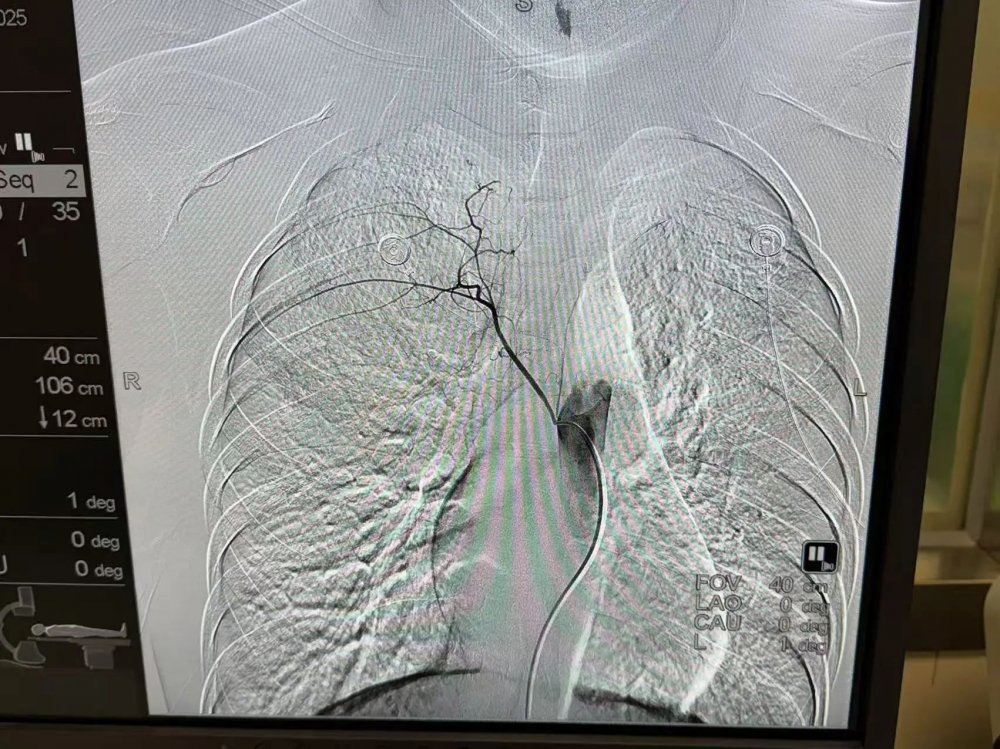

接到指令后,介入团队迅速到位。下午三点多,手术正式开始。术中,卜高峰通过股动脉穿刺,将导管精准插入责任血管,用栓塞材料“封堵”出血口,全程70分钟左右。术后患者咯血立即停止,生命体征平稳。

支气管动脉栓塞术(bronchial artery embolization,BAE)是一种微创血管介入技术,其基本原理是利用导管造影显示支气管动脉或非支气管性体动脉发现可能引起咯血的责任血管,通过导管将栓塞材料定向注入责任血管,同时减少血流量、降低远端血管压力,启动内源性和外源性凝血途径,继而促进局部血栓形成进一步达到止血目的。

2.精准靶向:DSA造影下锁定出血血管,误差小于1毫米;